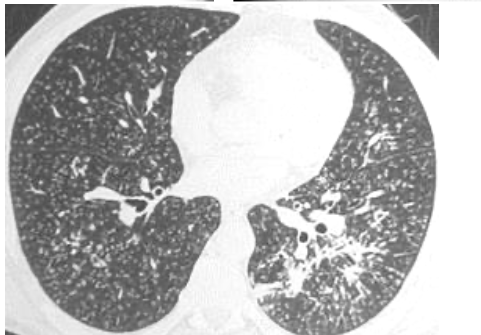

Mr Y vient en consultation pour dyspnée d'effort et toux sèche, à l'examen vous observez des râles crépitants (velcro) aux bases et l'existence d'un hippocratisme digital. Vous observez l'image suivante au scanner :

Quelle est votre principale suspicion ?

Fibrose pulmonaire idiopathique (FIP) :

-grands signes cliniques

-signes de TDM : kystes, réticulations, bronchectasies

-prédominance aux bases des signes (au TDM et les crépitants)